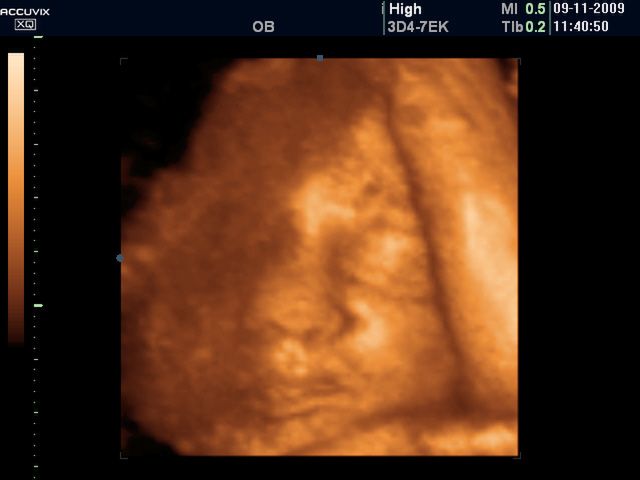

Z roku na rok wzrasta liczba porodów przez cesarskie cięcieZ roku na rok wzrasta liczba porodów przez cesarskie cięcie